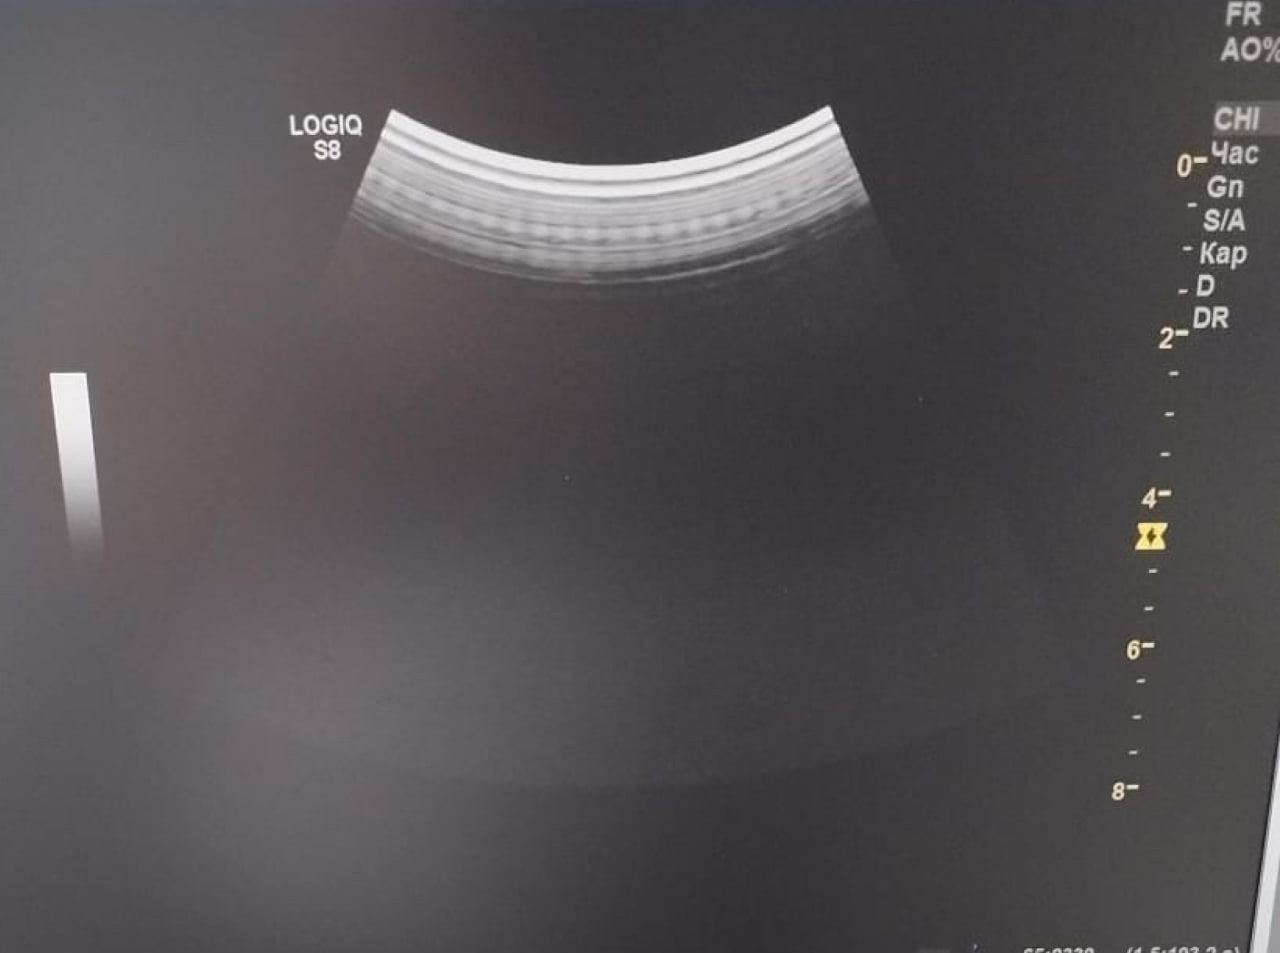

Выполнен компонентный ремонт: заменены дефектные элементы, отвечающие за обработку сигнала. После восстановления плата прошла проверку в условиях нагрузки. Изображение стабильное, помехи не проявляются. (На фото 2 результат работы)